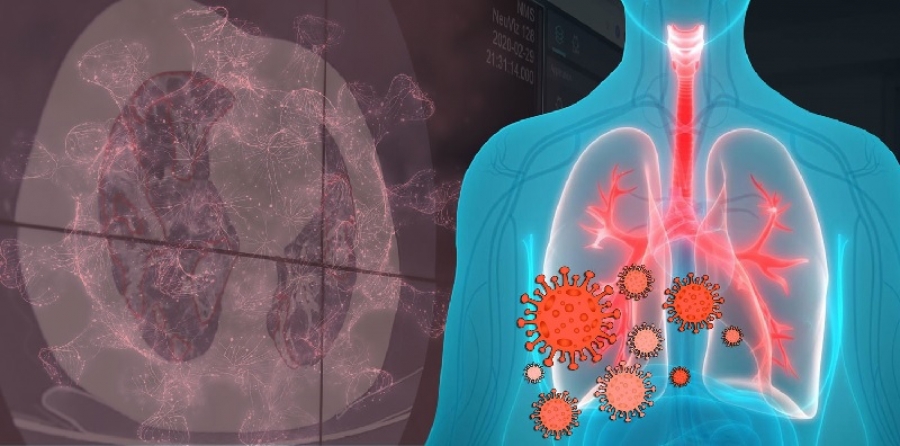

كيف يهاجم COVID-19 جسم الانسان؟

كيف ينتشر فيروس كورونا في الجسم؟

ينتقل الفيروس إلى أسفل الجهاز التنفسي. هذا هو مجرى الهواء الذي يشمل الفم والانف والحلق والرئتين. تحتوي المجاري الهوائية السفلى عند الإنسان على عدد أكبر من مستقبلات ACE2 من باقي الجهاز التنفسي مما يعطي الفيروس أفضلية في السيطرة على الخلايا السليمة. وبذلك يكون COVID-19 أكثر عمقا من الفيروسات الأخرى ولا تقف عوارضه عند نزلات البرد فقط. قد تلتهب الرئتين، مما يجعل من الصعب عليكم التنفس. كما يمكن أن يؤدي ذلك إلى الالتهاب الرئوي، وهو عدوى في الأكياس الهوائية الدقيقة (تسمى الحويصلات الهوائية) في المكان الذي يتبادل الدم الأكسجين وثاني أكسيد الكربون. بالنسبة لمعظم الناس، تنتهي الأعراض مع السعال والحمى. أكثر من 8 حالات من كل 10 حالات خفيفة. ولكن بالنسبة للبعض الآخر، تزداد العدوى حدة. بعد حوالي 5 إلى 8 أيام من بدء الأعراض، تشتد أعراض ضيق التنفس لتنتقل تدريجيا بعد بضعة أيام إلى متلازمة الضائقة التنفسية الحادة ARDS. وهنا يحتاج المريض إلى دخول غرفة الطوارئ للاستعانة بجهاز التنفس والحفاظ على حياته.